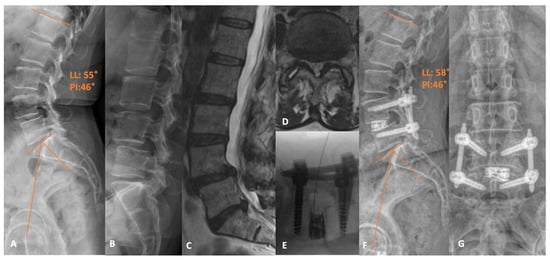

3. Open Transforaminal Lumbar Interbody Fusion

4. Minimally Invasive Transforaminal Lumbar Interbody Fusion